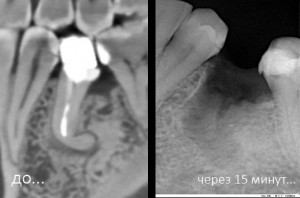

Синуслифтинг: что делать при перфорации слизистой оболочки гайморовой пазухи?

Перфорация (или повреждение) слизистой оболочки верхнечелюстной пазухи — наиболее частое осложнение при операции синуслифтинга. Но…. проблема, которую можно решить — уже не проблема. Верно?